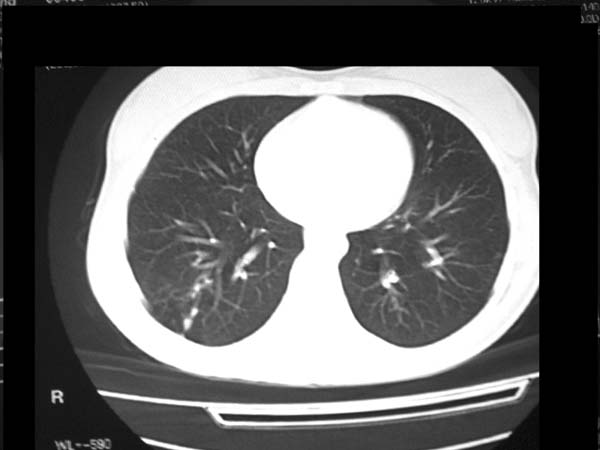

标题: CT13486:F 17Y 咳嗽 咳痰数日请会诊 [打印本页]

标题: CT13486:F 17Y 咳嗽 咳痰数日请会诊

白细胞9600不发烧

考虑右下结核球

右肺下叶结核灶

右下肺背段病灶,考虑结核与炎症鉴别,请进一步检查.

考虑为:右肺下叶外基底段结核球。

结果;痰中找到结核杆菌

痰涂片已找到结核杆菌  将结果告诉大家